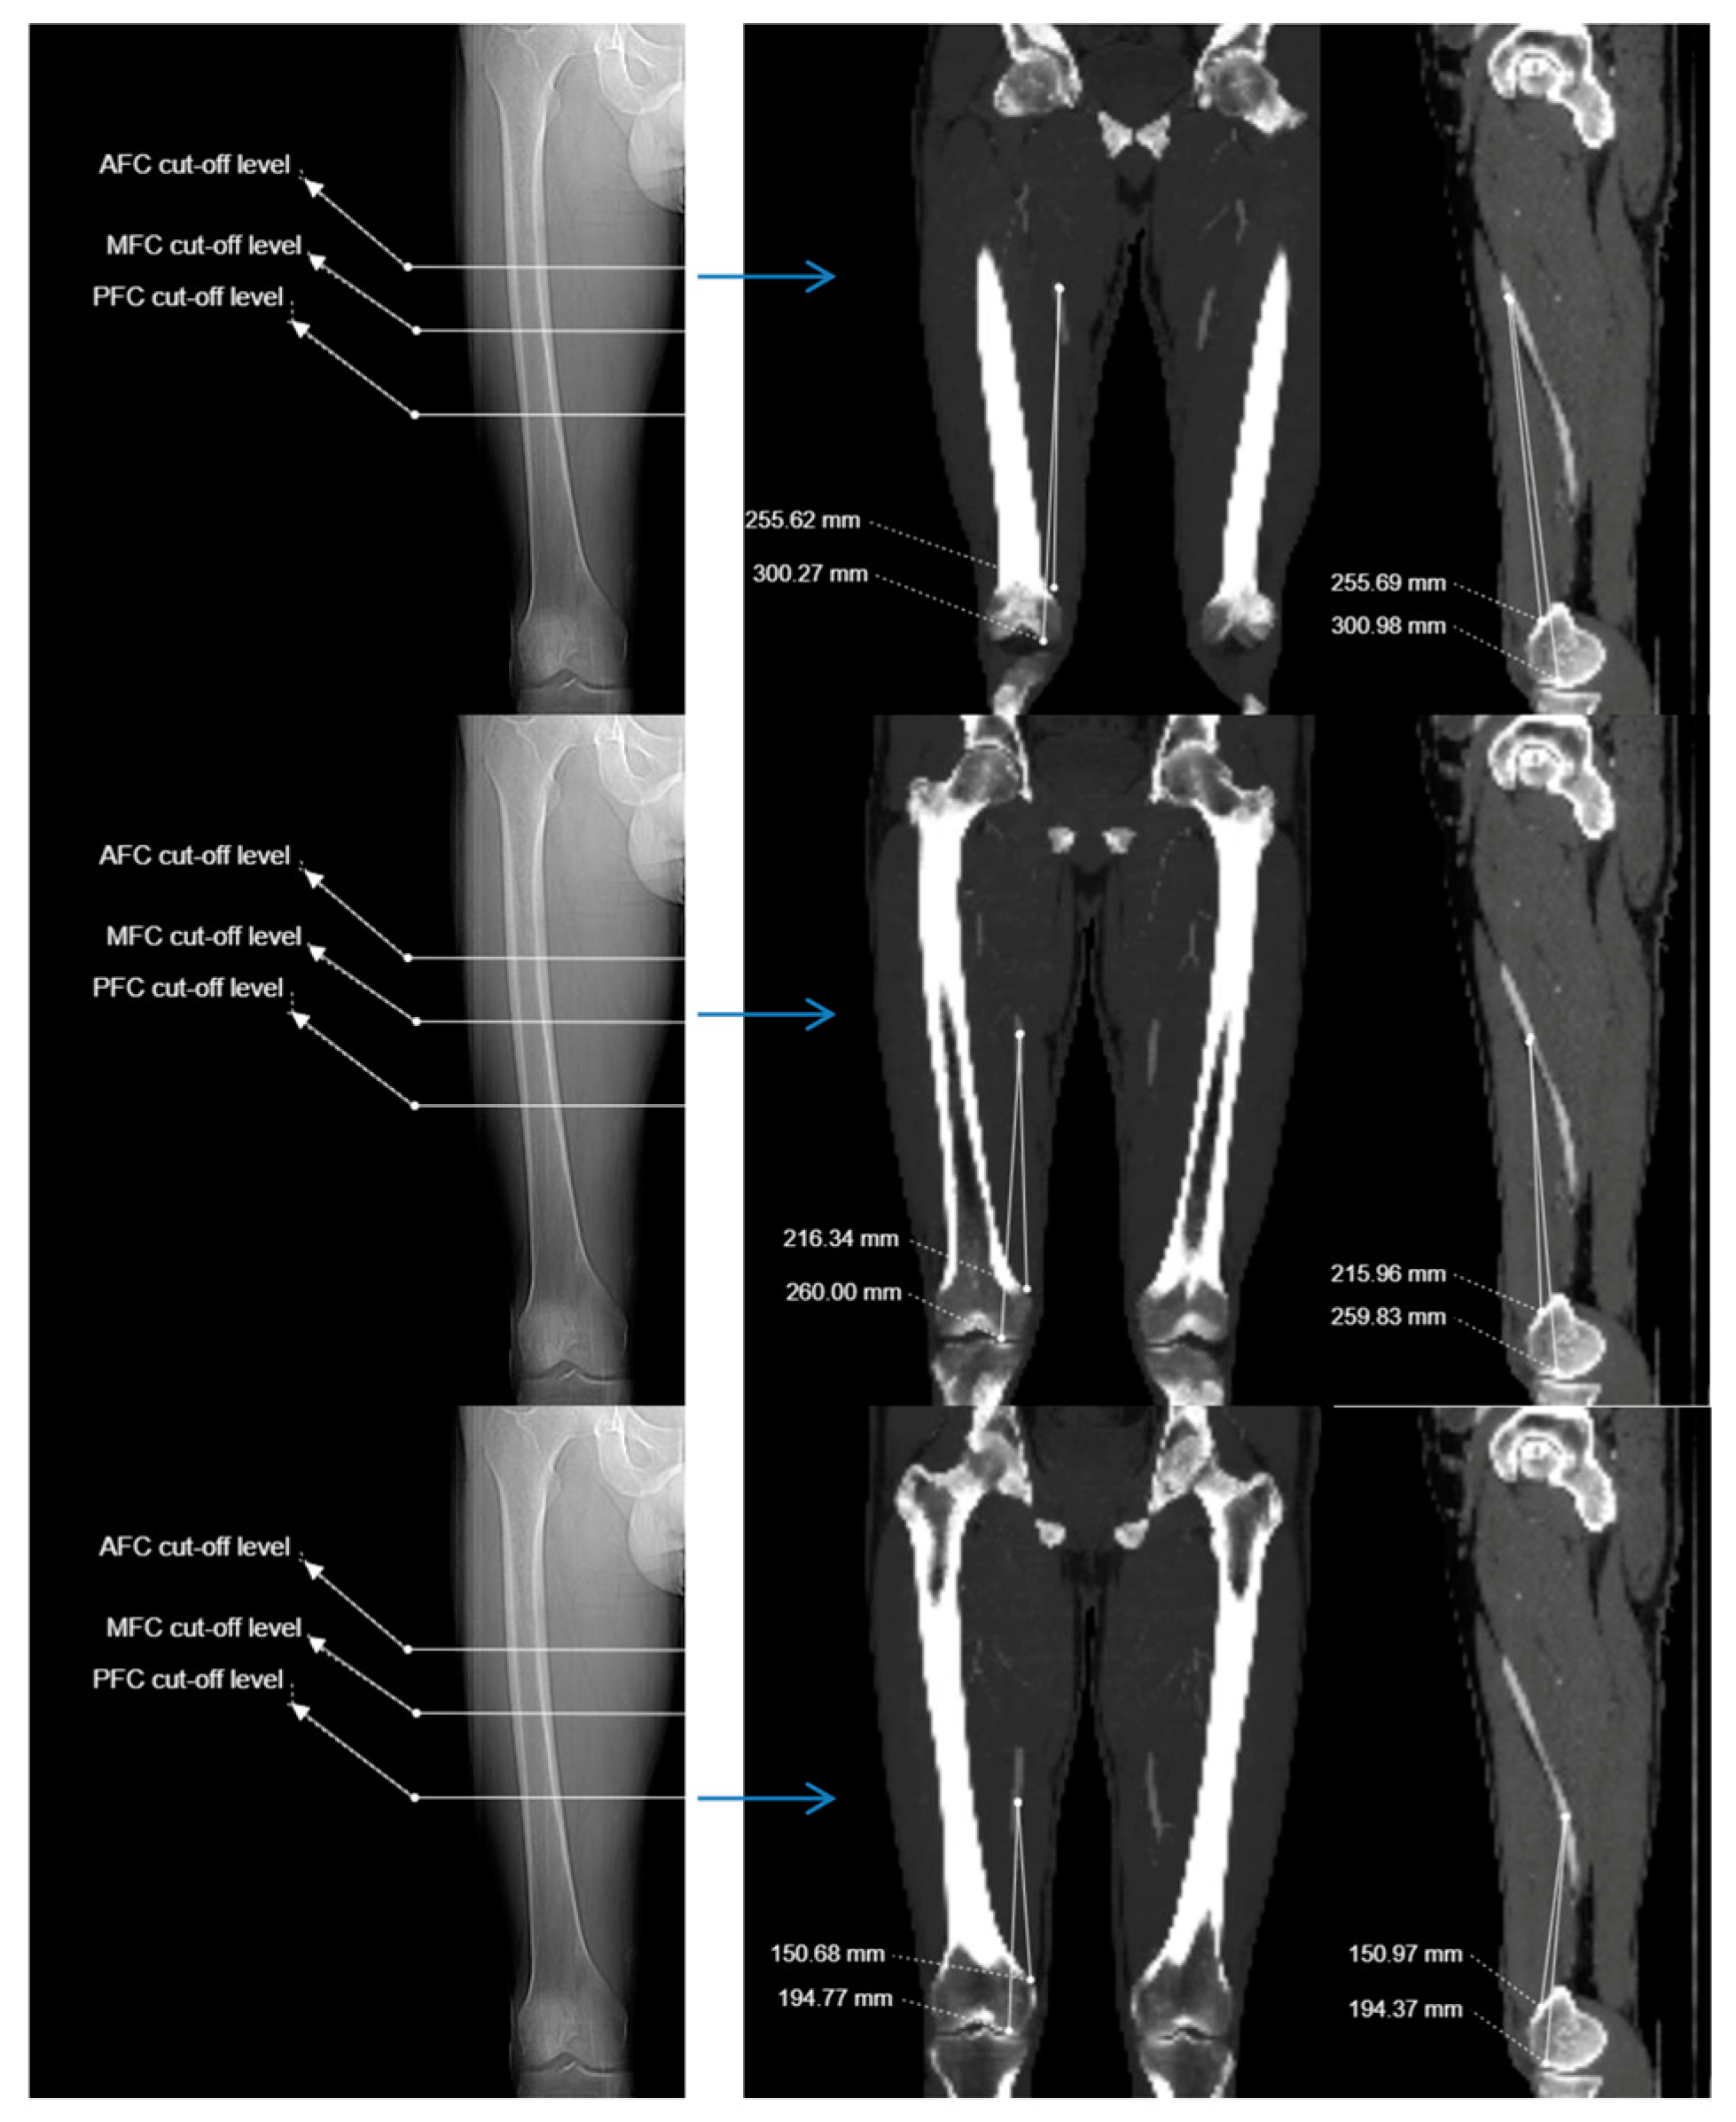

| Anterior femoral cortex | 223.01 ± 27.38 (156.3 - 293.8) |

265.04 ± 28.21 (207.0 -334.5) |

27.20 ± 5.32 (15.1 - 40.4) |

16.49 ± 9.94 (-9.7 - 40.5) |

| Midsagittal femoral cortex | 180.78 ± 26.83 (107.1 - 246.3) |

222.40 ± 27.65 (156.1 - 292.6) |

25.22 ± 5.52 (11.5 - 58.2) |

| Posterior femoral cortex | 128.01 ± 29.59 (54.1- 200.1) |

170.13 ± 29.96 (93.9 - 241.7) |

22.93 ± 6.04 (7.6 - 38.0) |

-36.58 ± 11.30 (-79.2 - -10.3) |